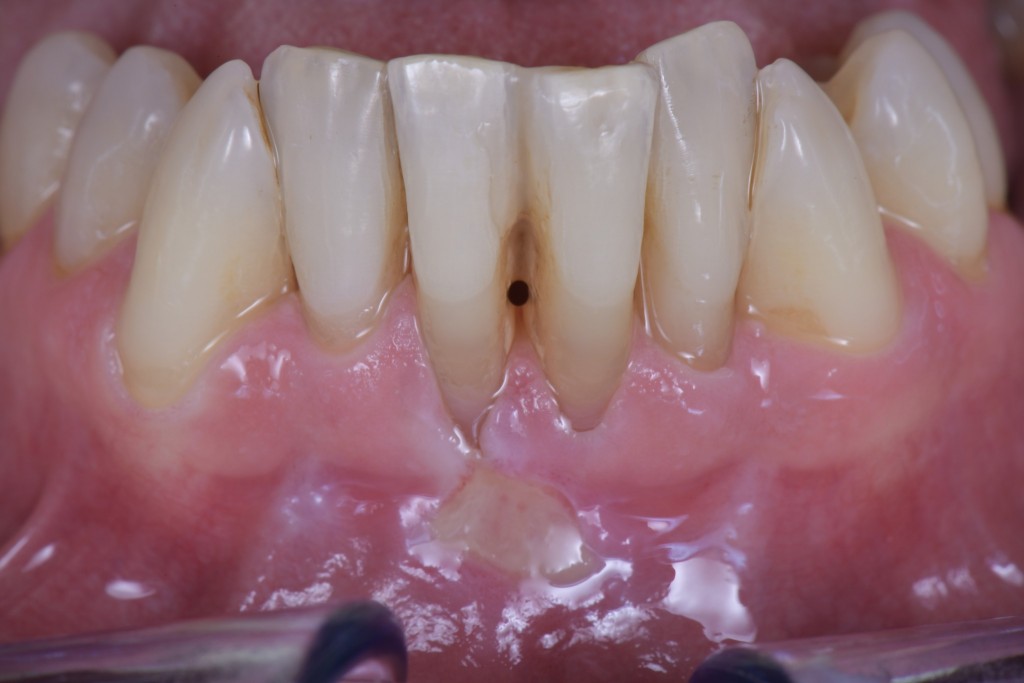

Il mio paziente si era presentato in visita con una ferita ricorrente da spazzolamento facilitata dalla scarsa qualità dei tessuti e dalla completa assenza di tessuto cheratinizzato.

In un caso del genere, vista la grave perdita di attacco, una ricopertura radicolare completa sarebbe ovviamente impossibile ed una ricopertura parziale sarebbe difficilmente predicibile nel risultato. Dopo la terapia causale e le istruzioni d’igiene con conseguente risoluzione della lesione, ho allora deciso di limitarmi a creare una banda di tessuto cheratinizzato che consentisse al paziente di spazzolare sereno…